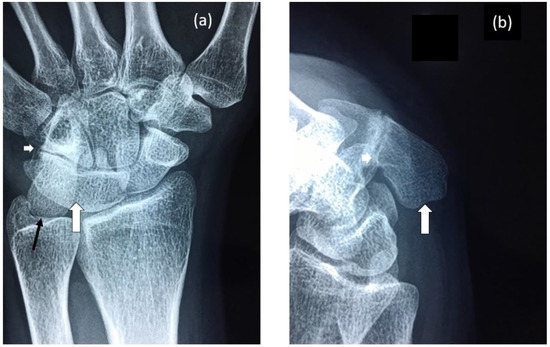

3.1.1. Female Proband (IV-12)

| Proband (IV-12) | F | 0–27 | Carpal Tarsal Coalition, Pisiform elongated No hearing impairment or congenital vertebral fusion, Postnatal vertebral fusion, speech impaired, short tongue and microstomia. |